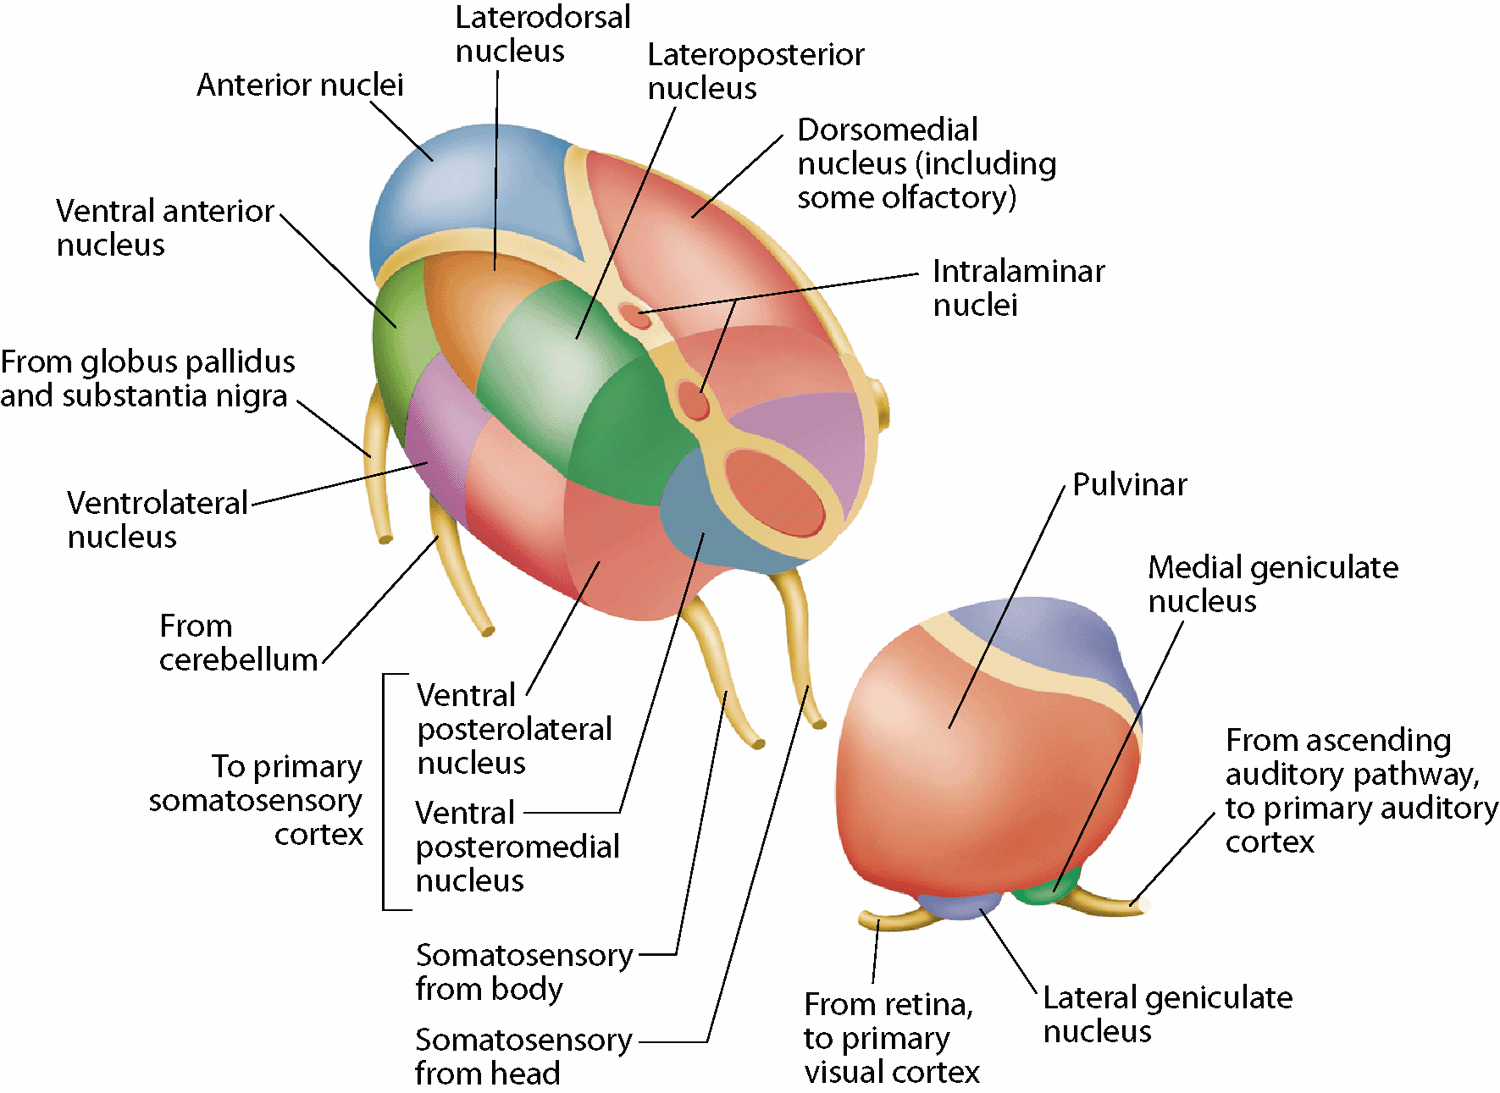

Differences in mechanosensory discrimination across the body surface

- The accuracy of our sense of touch is not the same all over the body

- Can use two-point discrimination tests to show this

- Fingers can distinguish things 2 mm apart, forearms 40 mm apart

- Mechanosensory receptors are more numerous in finger tips and have smaller receptive fields

- Doesn't explain everything about ability to discriminate two points. The CNS is also involved with discrimination. Two point thresholds vary with practice, and depend on the stimulus

Receptive field size across the body surface

- Receptive field (RF)– the area in the periphery within which sensory stimulus can modulate the firing of the sensory neuron

- Spatial resolution of the RF:

- Size– smaller RF, higher resolution

- Density– higher cell density, higher resolution

- Two-point discrimination test